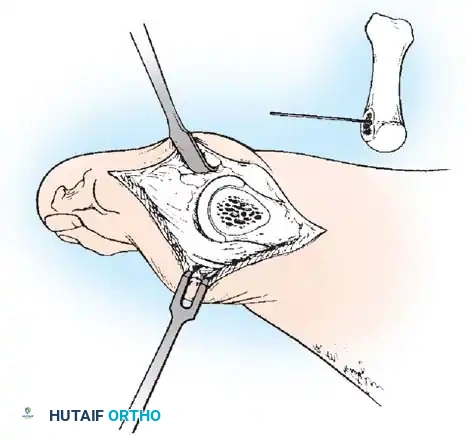

REMOVAL OF THE FIBULAR SESAMOID

• When the medial eminence and phalangeal base have been excised, remove the fi bular sesamoid.

• Place a sturdy two-toothed retractor beneath the metatarsal head, and have an assistant lift it dorsally.

• Using a Freer elevator or a small osteotome for its strength, mobilize the fi bular sesamoid (Fig. 78-31A to C). This may be diffi cult in elderly patients with signifi cant deformity and adherence of the sesamoid to the metatarsal head. Lift the metatarsal dorsally for exposure (Fig. 78-31D and E).

• When the sesamoid is mobile, identify the fl exor hallucis longus tendon by placing traction on the hallux and fl exing and extending the interphalangeal joint of the hallux. The tendon is visible just distal to and in alignment with the sesamoids, which straddle it.

• Identify and expose the lateral neurovascular bundle just lateral to the tendon by blunt dissection.

• Pull the plantar medial capsule medially. This requires a fi rm grasp on the capsule. The medial traction brings the intersesamoid “ligament” into better view.

• Incise the intersesamoid ligament longitudinally with a No. 67 Beaver or No. 15 Bard-Parker blade. If tenotomy scissors are used, place one arm of the scissors under the ligament (this arm rests on the dorsal side of the fl exor hallucis longus) and the other arm dorsal to the ligament.

• When the intersesamoid ligament is incised, grasp the sesamoid fi rmly with forceps or a small Kocher clamp, fl ex the toe at the interphalangeal and metatarsophalangeal joints to relax the fl exor hallucis longus tendon, and pull the fi bular sesamoid distally and medially.

• With release of the intersesamoid ligament, the medial surface of the fi bular sesamoid is free from soft tissue. Distally, the sesamoid is free because of resection of the base of the proximal phalanx. This leaves two sides of the sesamoid, distal and medial, free of soft tissue.

• While pulling the sesamoid distally and medially, use a small blade to incise along the lateral margin of the sesamoid under direct vision. Keep pulling the head of the metatarsal dorsally and holding the hallux distracted and in fl exion. This greatly aids in identifi cation of the margins of the fi bular sesamoid, particularly laterally and proximally.

• The most diffi cult part of the sesamoidectomy and that which should be done last is release of the proximal lateral corner of the sesamoid where the fl exor hallucis brevis lateral head inserts. While incising the lateral capsular attachments to the sesamoid, do not bury the blade of the knife because the neurovascular bundle to the lateral side of the hallux is just lateral to the capsule.

• Now all attachments to the fi bular sesamoid have been removed except the lateral head of the fl exor hallucis brevis, which inserts on the proximal lateral margin of the sesamoid. This is a diffi cult section to remove; however, this section can be released under direct vision by pulling the sesamoid distally and medially and lifting the metatarsal head dorsally with a strong two-toothed retractor.

• When the sesamoid has been removed, insert two 0.062-inch Kirschner wires retrograde from the tip of the toe 2 to 3 mm plantar to the nail bed, leaving about 5 to 7 mm of the pins exposed at the base of the phalangeal remnant to help align the phalanx on the metatarsal before antegrade passage of the pins into the metatarsal (Fig. 78-31F).

Fig. 78-31 Excision of fi bular sesamoid in modifi ed Keller procedure. With base of proximal phalanx removed and medial eminence excision, exposure of fi bular sesamoid is not as diffi cult from medial incision. A, Operative photograph showing elevation of fi rst metatarsal with strong two-tooth retractor and use of small osteotome to mobilize fi bular sesamoid and lateral capsuloligamentous (frequently contracted) structures. Osteotome is between metatarsal head and lateral sesamoid. When mobilization of fi bular sesamoid is complete, entire sesamoid is visible for excision. Note chondromalacia of tibial sesamoid articular surface medial to osteotome. B, Fibular sesamoid has been excised, and lateral capsular structures and conjoined tendon (in forceps) have been released. Neurovascular bundle to lateral side of hallux is adjacent to these structures. C, Diagrammatic representation of modifi ed Keller procedure. By excising fi bular sesamoid, valgus moment of conjoined tendon of fl exor hallucis brevis and adductor hallucis no longer pulls fl exor hallucis longus tendon laterally (carrying hallux with it) through capsulosesamoid plantar plate and pulley system. D, Metatarsal head must be lifted dorsally to excise fi bular sesamoid under direct vision. E, Note exposure of fi bular sesamoid after mobilization of metatarsal head. Continued